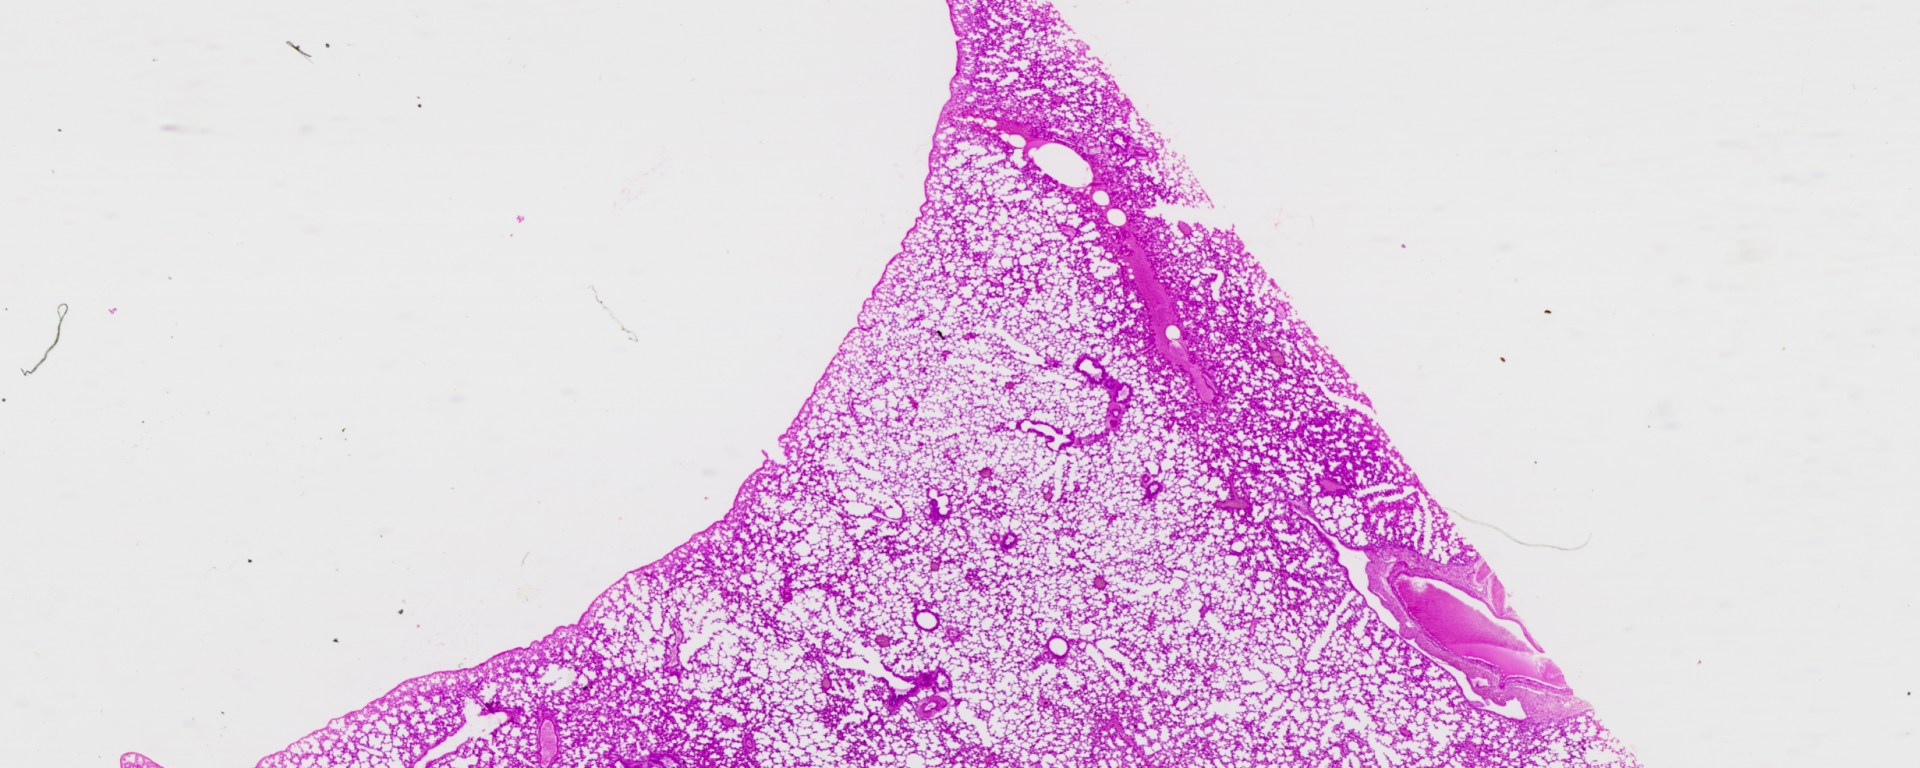

Lung human.jpg

Human Lung (TM: ~2.5x, picture taken with a Nikon Coolscan V slide scanner)